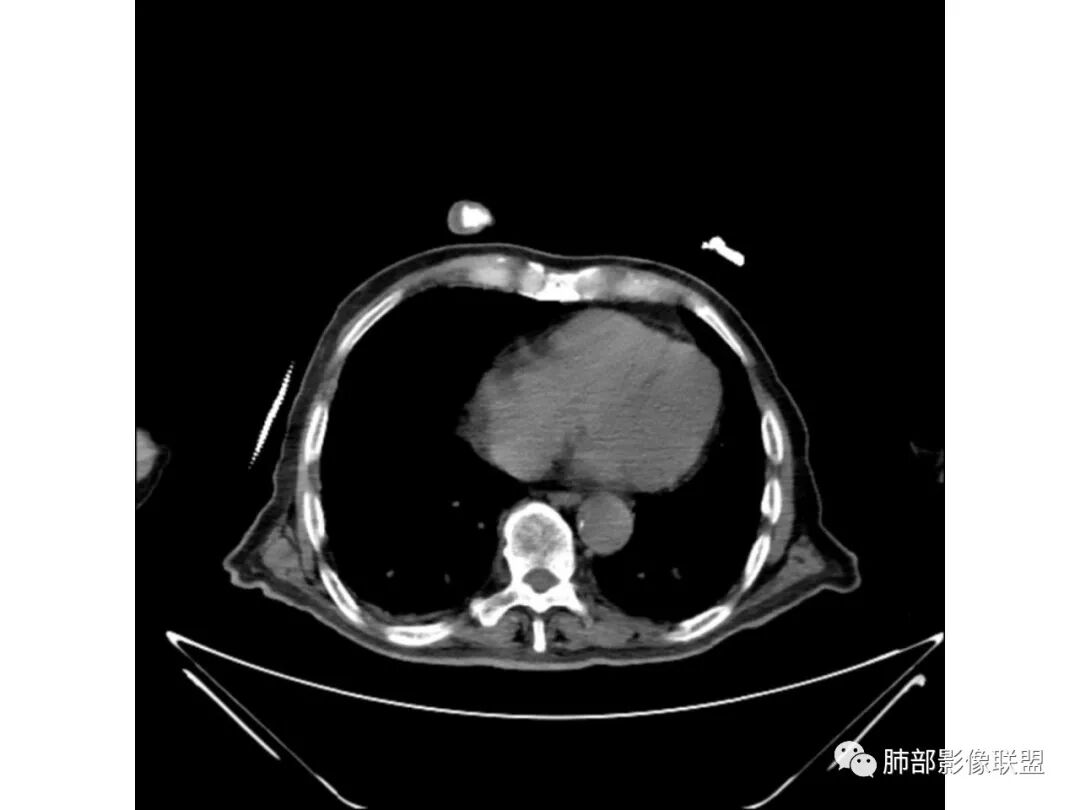

老年男性,有糖尿病病史,右侧胸廓塌陷,肺容积缩小,右肺上叶片状实变密度影及高密度影,边缘模糊,内可见支气管充气征及多发虫蚀样空洞,考虑结核可能大。肝脏只有一层,看上去正常

总体分析就是不符合恶性。蜂窝、空洞与肺气肿有关,支气管主要还是远端稍扩张

南边:

肺炎型肺癌——支气管远端狭窄或堵塞为主

外围的支气管不会这么大,而且越到远端越小,这个不符合,所以考虑稍扩张

炎性:糖尿病有哪些可能?

炎性:结核、毛霉菌、肺克雷白杆菌、金葡菌

单发在右上叶,好发的病变:结核、肺克雷白杆菌。

支气管、内部的小囊腔,部分无壁小空洞,病灶部分边界偏清,支持结核

曲霉菌,一般是气道的,较广泛,不局限,慢阻肺病人可能影像表现不明显。

结核放在首位,其他的待排。